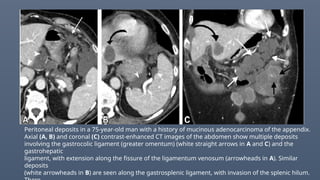

Peritoneal deposits in a 75-year-old man with a history of mucinous adenocarcinoma of the appendix.

Axial (A, B) and coronal (C) contrast-enhanced CT images of the abdomen show multiple deposits

involving the gastrocolic ligament (greater omentum) (white straight arrows in A and C) and the

gastrohepatic

ligament, with extension along the fissure of the ligamentum venosum (arrowheads in A). Similar

deposits

(white arrowheads in B) are seen along the gastrosplenic ligament, with invasion of the splenic hilum.